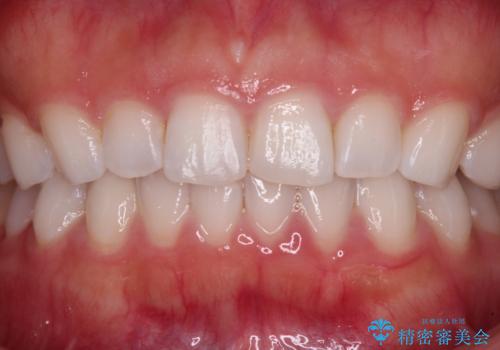

むし歯はなく、矯正治療で咬み合わせが改善していたので、侵襲量の少ないラミネートベニアにて治療することとしました。

ラミネートベニアは切削量が少ないことがメリットとしてあげられますが、色調を周辺と合わせられないこと、接着境界線が長く汚れや歯石が溜まりやすいことがデメリットとして考えられます。

また、接着境界線にむし歯がある場合には適用外となるなど、適用症例を選ぶため、治療に際して担当医としっかりと相談することが大切です。